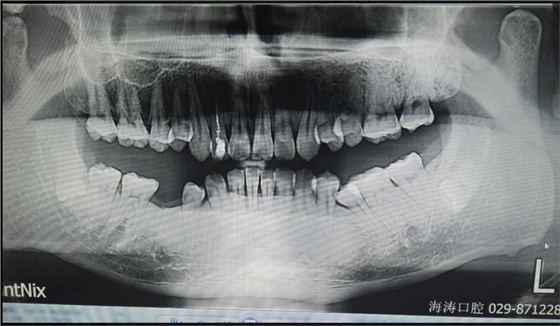

討論四:片子顯示的倒置阻生牙撥牙關(guān)健注意幾點,1.翻瓣后去骨部位盡量離7遠中,別破壞7遠中骨壁,避免損傷7,以去除8根部的阻力為主。2.暴露阻生牙后,用鉆磨斷部分冠根后,用小骨鑿劈裂冠與根,可避免牙鉆因視野而誤傷神經(jīng)。3.冠根裂開后,先用牙挺挺出根部,然后挺出冠部。